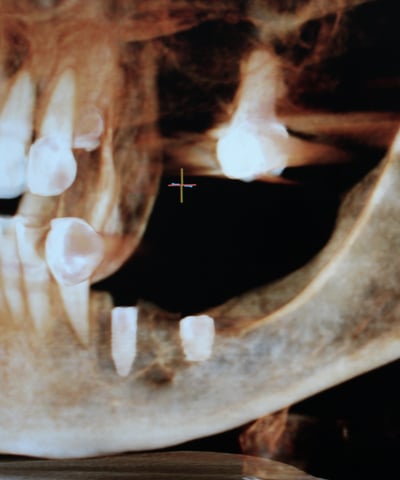

Comprometidos con la excelencia, enseñamos técnicas innovadoras en implantología y cirugía oral, formando a los futuros referentes del sector. Ofrecemos diferentes posibilidades de formación: online y presencial, damos formación para aquellos doctores que quieren aprender a hacer cirugía guiada sin fabricarse sus propias guias, y por otro lado damos formación para los doctores que quieren aprender las dos cosas, realizar cirugía guiada, y fabricarse sus propias guías quirúrgicas.

Capacitación en técnicas de cirugía guiada para cirujanos.